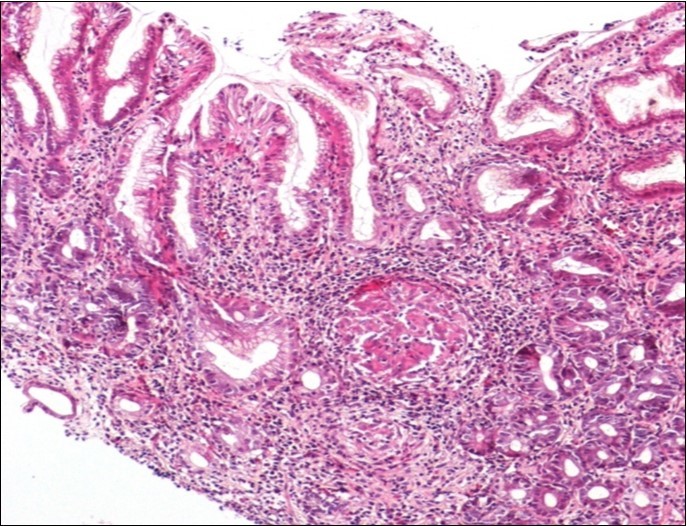

Concerning the etiology, diagnosis was made regarding to the past medical facts, the clinical symptoms, the endoscopic findings and the histological associated lesions. The main etiology was represented by Crohn’s disease in ten cases, followed by gastric tuberculosis in 6 cases. H Pylori was the retained cause of gastric granulomatosis in 5 cases, regarding to the absence of other etiologies, and the favorable issue after antibiotic eradication treatment. In 5 other patients, etiology of gastric granulomatosis was also found and the final diagnosis was a sarcoidosis (n=3), foreign body reaction (n=1), and yersiniosis (n=1). In our series, thirteen cases were unclassifiable despite etiological investigations and no cause of gastric granulomatosis was isolated. Histological findings of a case of tuberculosis and sarcoidosis are represented in Figure 1 and Figure 2.

Figure 1.Histological aspect of gastric granulomatosis secondary to tuberculosis : Antral biopsy specimens revealing multiple necrotizing (caseating) granulomas ( HEx100)

Figure 2.Histological aspect of gastric granulomatosis secondary to sarcoidosis : Antral biopsy specimens revealing multiple non-necrotizing (sarcoid-like) granulomas ( HEx200)